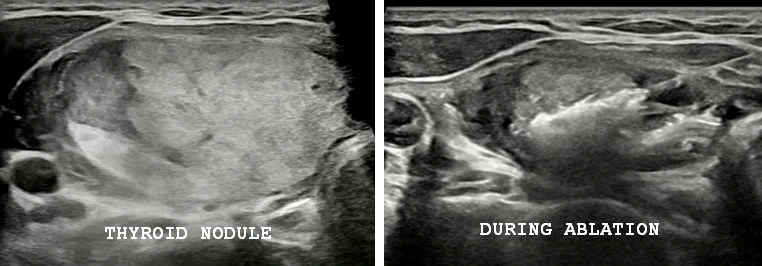

Thyroid nodule ablation is performed through a needle-based, image-guided technique, without any surgical incision. Under ultrasound guidance, a thin probe is inserted into the thyroid nodule, and controlled energy is delivered to ablate the nodule tissue.

The procedure is typically performed under local anesthesia and lasts about 30–60 minutes. Recovery is quick, with most patients returning to normal activities within one to two days. The treated nodule gradually decreases in size over the following weeks.